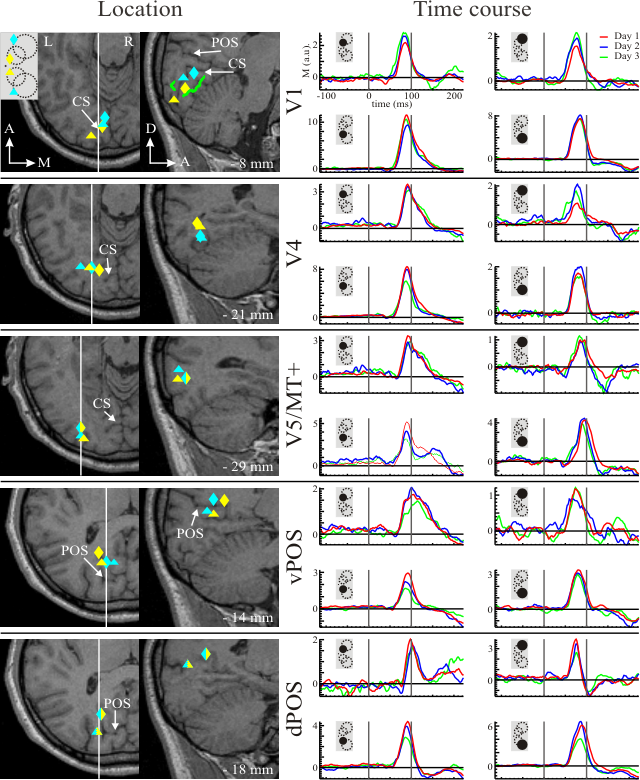

Three male subjects participated in the experiment where checkerboard pattern stimuli were presented at eight different locations in the parafoveal and peripheral visual fields. For each subject the same experiment was repeated on three different days, months apart. The precision of the localization was defined as the SD of the activation locations across three experimental days.

Responses in areas V1, V4, V5/MT+, vPOS and dPOS. ROI centres identified in the left hemisphere in response to right hemifield stimulations. The solid gray line on each axial MRI slice together with the X Talairach coordinate in the lower right corner for each area indicate the location of the corresponding sagittal slice. White arrows point to the parieto-occipital sulcus (POS), and calcarine sulcus (CS). Insert in the upper left corner shows the schematic image of the stimuli. Coloured symbols are depicted to indicate the correspondence between the stimulated locations, and identified ROIs; they were not presented to subjects. Triangles and diamonds indicate lower and upper; and cyan and yellow, peripheral and parafoveal visual field stimulations, respectively. The green lines on the sagittal slice showing the localization results for V1 indicate the V1/V2 borders (representation of vertical meridian), which were obtained in a separate fMRI experiment. ROI timecourses for three days (red - Day 1, blue - Day 2, green - Day 3) are superimposed. The black, filled circle in the schematic image of stimuli displayed on the upper left part of each figure indicates the stimulated location of the visual field for the timecourses displayed in that figure. POS, parieto-occipital sulcus; vPOS, ventral POS; dPOS, dorsal POS.

The localization precision was typically within 2 mm in all areas (V1, V4, V5/MT+, vPOS and dPOS). We identified also the precise timing of these areas, which was very reproducible across different experimental days. POS, parieto-occipital sulcus; vPOS, ventral POS; dPOS, dorsal POS.

V. Poghosyan, A. A. Ioannides, Neuroimage 35, 759-770 (2007). PDF >>